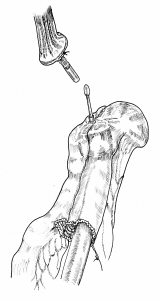

器械吻合器テクニックあれこれ

あのころ、実用化されたばかりの自動吻合器の使用上の「コツ」シリーズ。